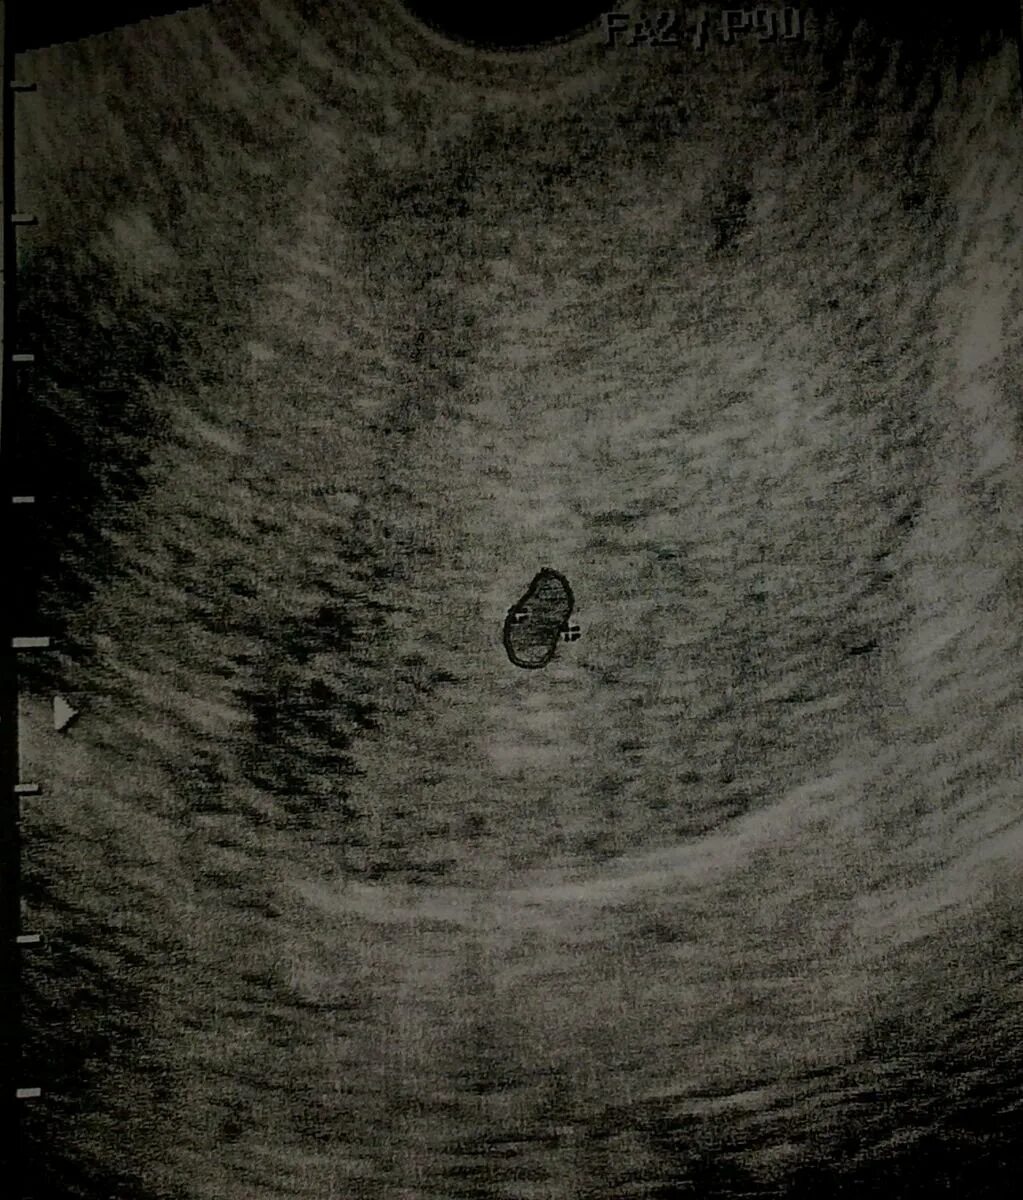

Плодное яйцо 3 мм